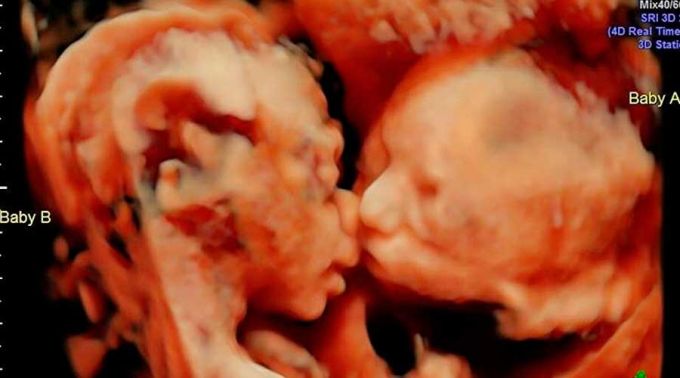

Ultrassom mostra bebê beijando a sua irmã gêmea

Nela aparecem duas irmãs gêmeas, uma beijando a outra.

Uma das gêmeas univitelinas surge em uma imagem de ultrassom dando um beijo na sua irmã.

A foto foi publicada pela mãe das meninas, Nathália Gentil Thomazelli, que está grávida de 36 semanas.

Em uma publicação feita no Instagram, ela falou que as duas filhas estavam de cabeça para baixo no último ultrassom. Mas no exame mais recente, as duas aparecem sentadas com as cabeças encostadas. De repente a médica flagrou um dos bebês beijando o outro.

De acordo com Nathália, a mãe das gêmeas, a médica responsável pelo seu pré-natal sempre faz uma imagem 3D no final do exame e que foi uma grande surpresa ver suas filhas assim.